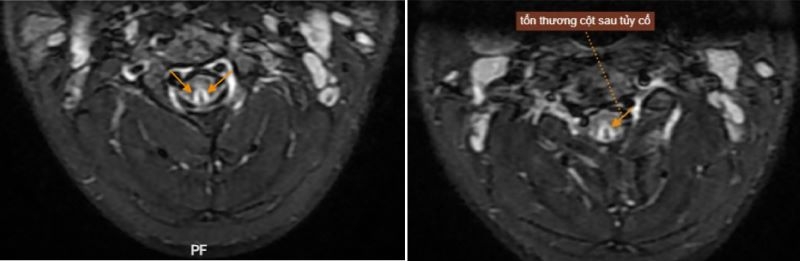

Dựa trên các biểu hiện lâm sàng, bệnh nhân được chỉ định thực hiện các xét nghiệm chuyên sâu, đo tốc độ dẫn truyền vận động, cảm giác và chụp cộng hưởng từ (MRI) vùng cổ.

| Hình ảnh MRI của bệnh nhân phát hiện tổn thương sau tủy cổ |

Đáng chú ý, hình ảnh MRI phát hiện tổn thương cột sau tủy cổ, kéo dài từ đốt sống cổ thứ hai đến đốt thứ sáu - một tổn thương điển hình thường gặp ở người lạm dụng khí N₂O kéo dài.

Bệnh nhân được chỉ định điều trị ngoại trú theo đơn thuốc, đồng thời cần tái khám định kỳ để theo dõi tiến triển, chụp lại MRI sau 3-6 tháng nhằm đánh giá mức độ phục hồi của tổn thương tủy cổ.